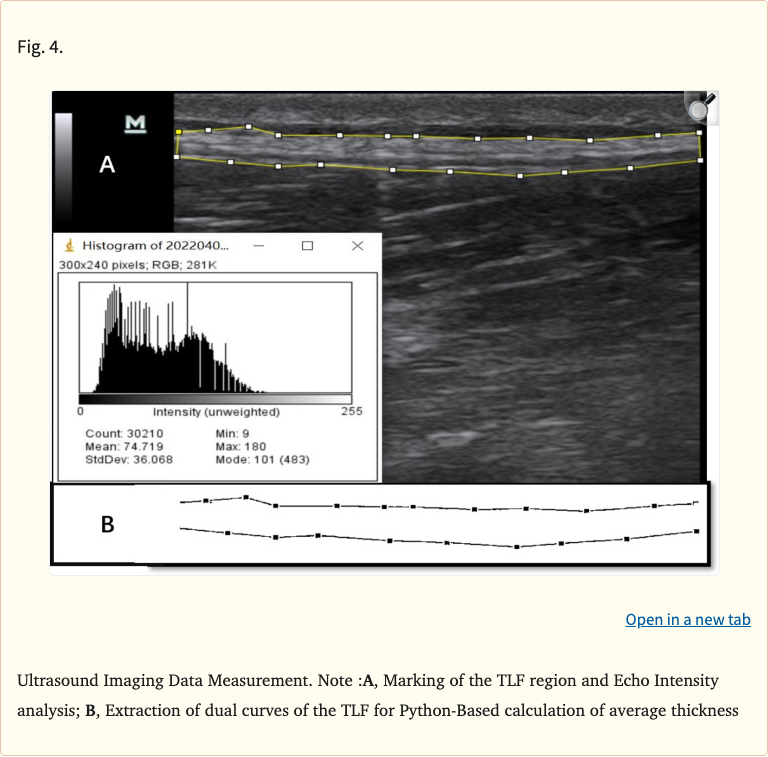

The researchers used ultrasound imaging to measure thoracolumbar fascia thickness and echo intensity, a marker of fascial tissue quality where higher echo intensity indicates more fibrosis or disorganization. Both groups were assessed at baseline, post-intervention, and at 4-week follow-up.